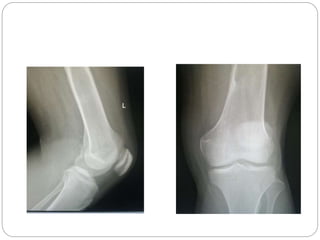

This document discusses 8 oncology cases. Case 1 involves a 40-year old female with right knee pain. Case 2 is a 28-year old male with a left subtrochantric fracture from a MVA who is now experiencing increasing left knee pain and swelling. Biopsy results showed high-grade osteosarcoma. Case 3 is a 30-year old female with breast cancer and bone metastases causing bilateral hip pain.